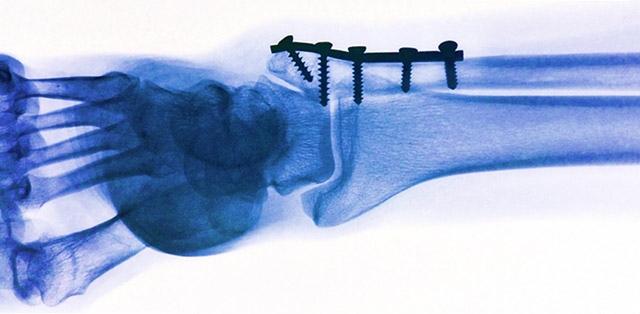

常规的由钛或钢制成的金属植入物在骨折后能将骨头碎片稳定地固定在一起。但是,它们不会溶解。需要执行另一项操作才能将其删除。图片来源:pixabay

当外科医生想在骨折后固定骨碎片时,关键的问题是要使用哪种植入物:钛或钢制成的螺钉和板在体内机械和化学上非常稳定,但随后必须将其卸下。另一个手术程序?还是由有机材料制成的植入物会随着时间的流逝而溶解,但可能还会有其他一些缺点,例如机械强度不足或降解产物不利? Empa研究人员目前正在努力解决这一难题:微小的镁植入物和螺钉。它们起初在机械上很坚固,但随后以可控制的方式在体内溶解,不会引起组织损伤。